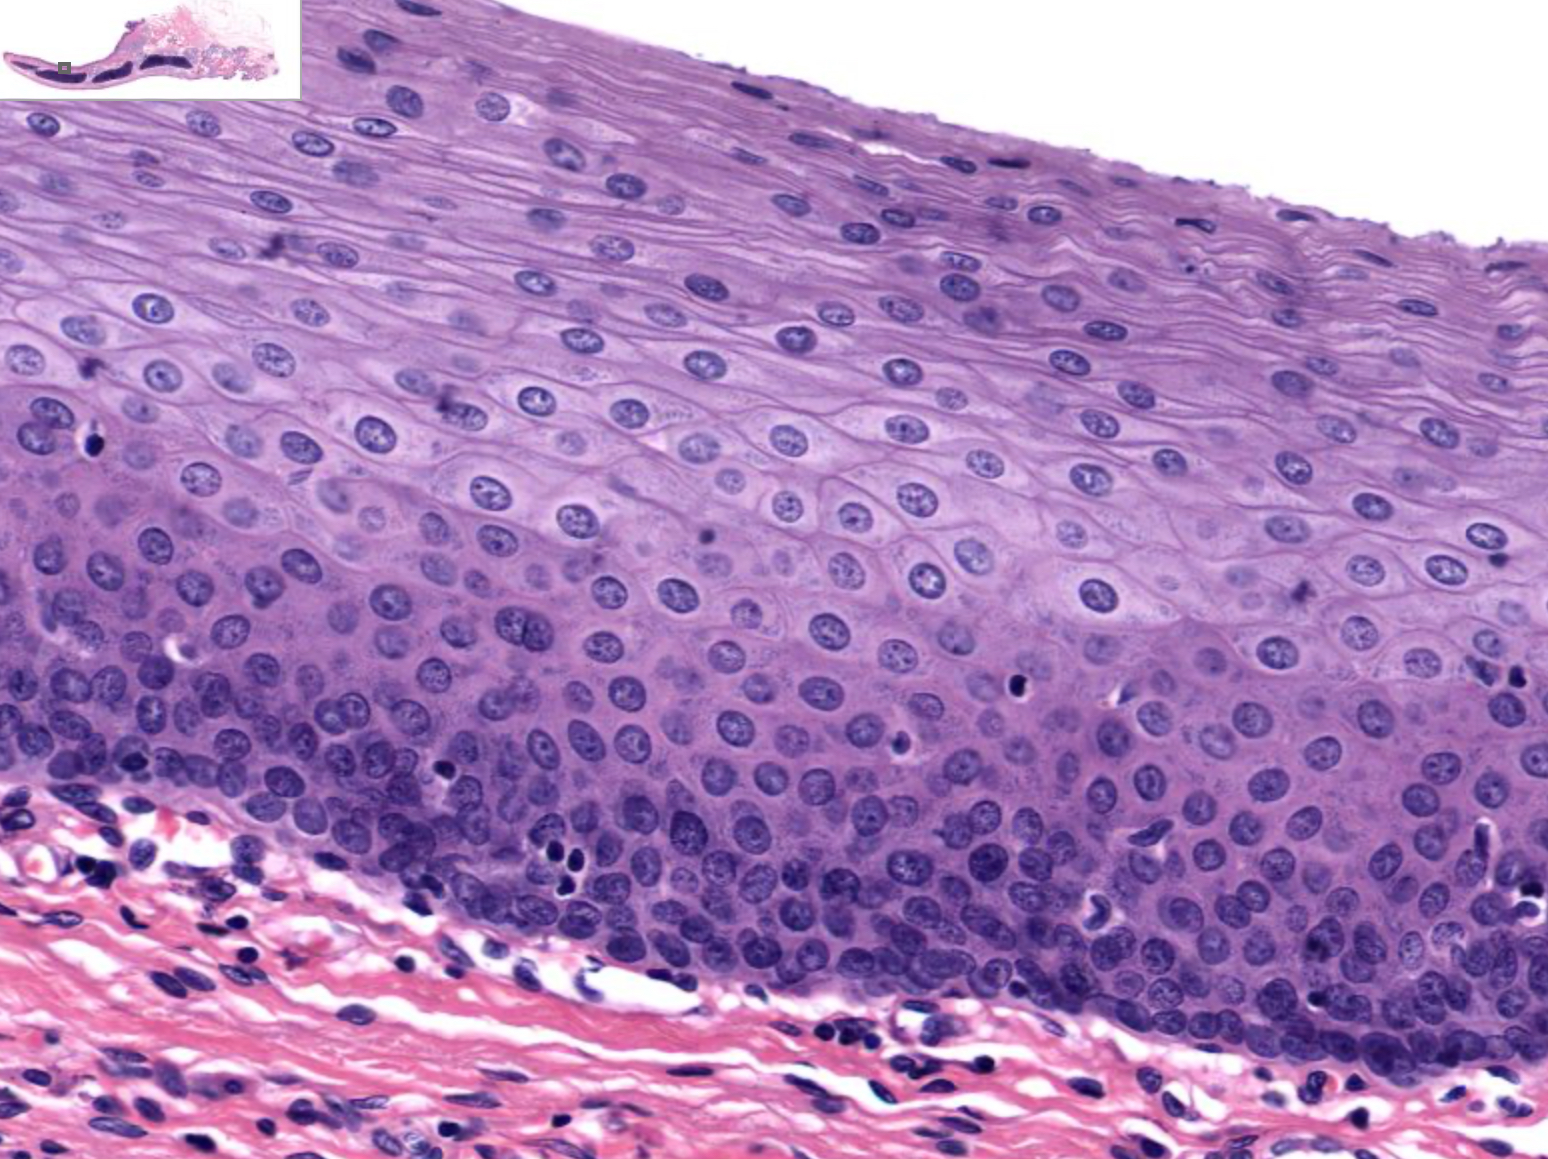

Tissue: relaxed transitional epithelium

Location: Lower Urinary Tract

also in: ureters, urinary bladder, part of urethra

Function:

• stretches and permits distention